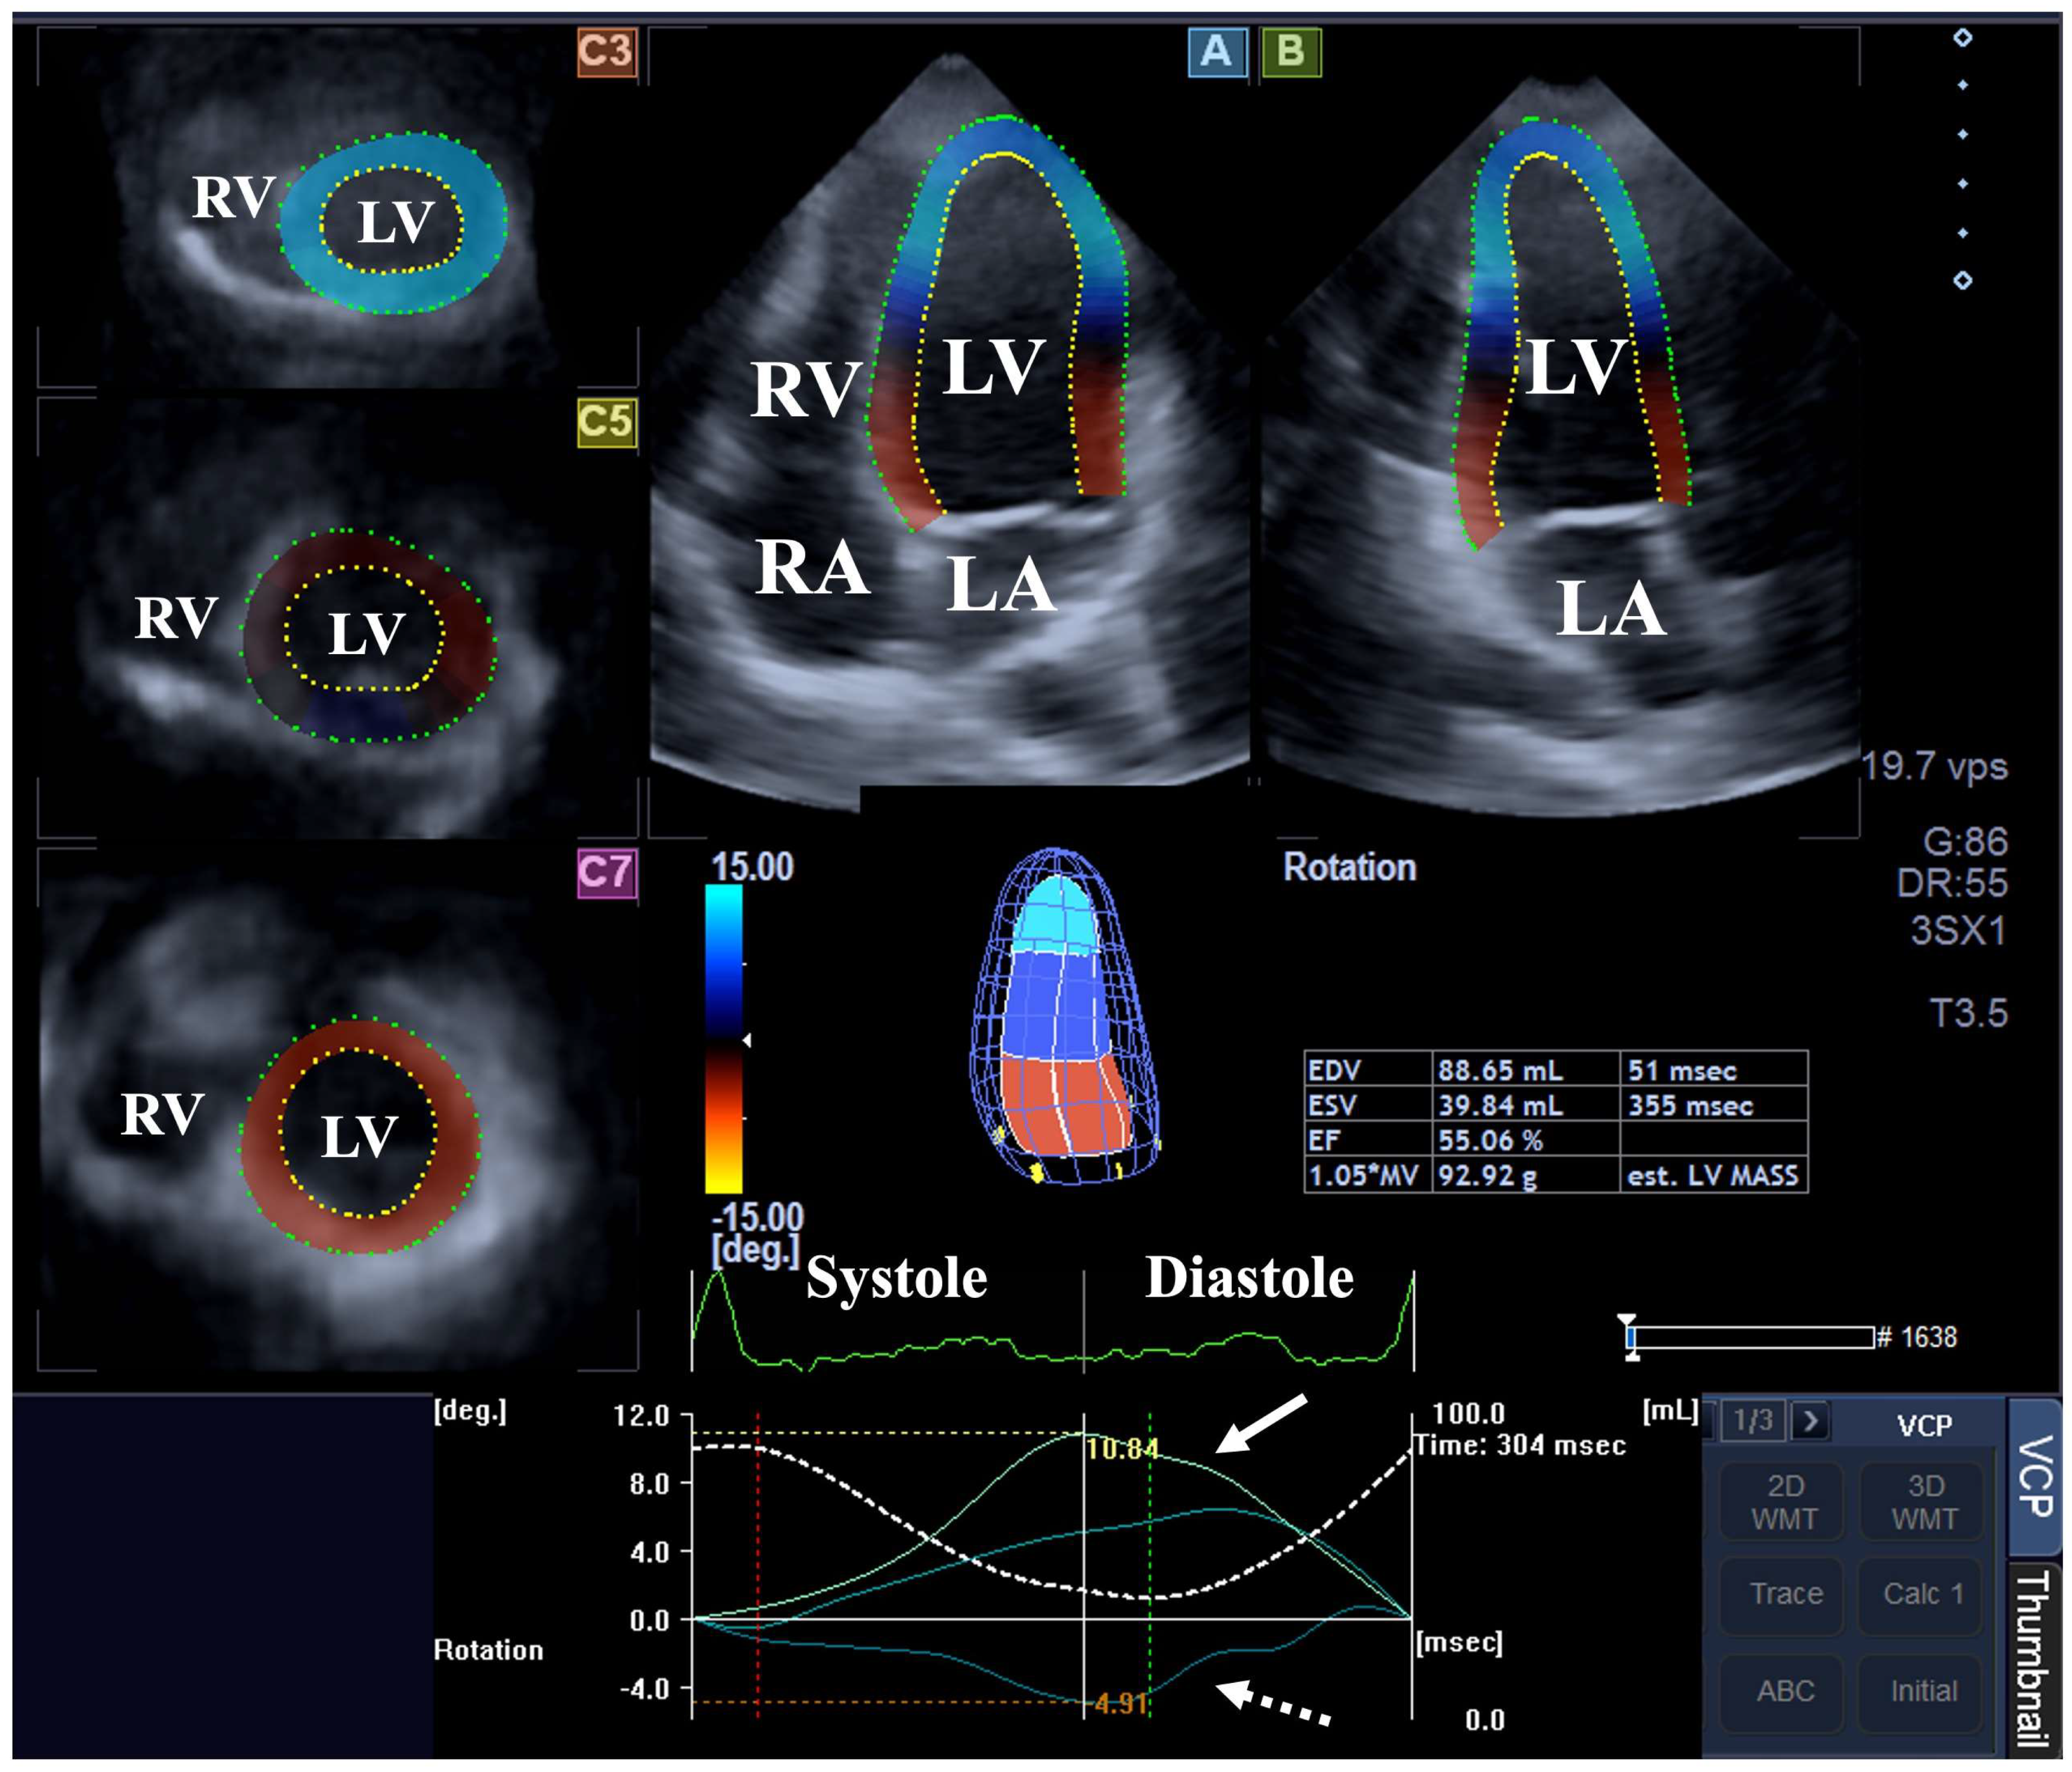

2. Materials and Methods